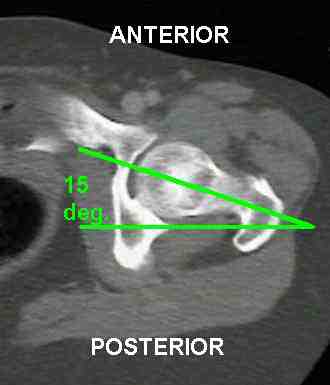

Anteversion is an angular measurement that relates the femoral neck's position or posture to the frontal plane. The figure (Wheeless, 1996) illustrates the anteversion angle.

Typical angles for both measures are 15 degrees. Antetorsion is measured clinically by Ryder's test (Cusick & Stuberg, 1992).